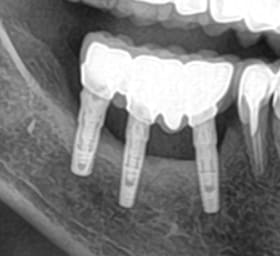

J'ai besoin de votre aide afin d'identifier les implants de mon patient.

Navrée, aucune rétro alvéolaire.

Mais si qqun à une piste. Je suis preneuse